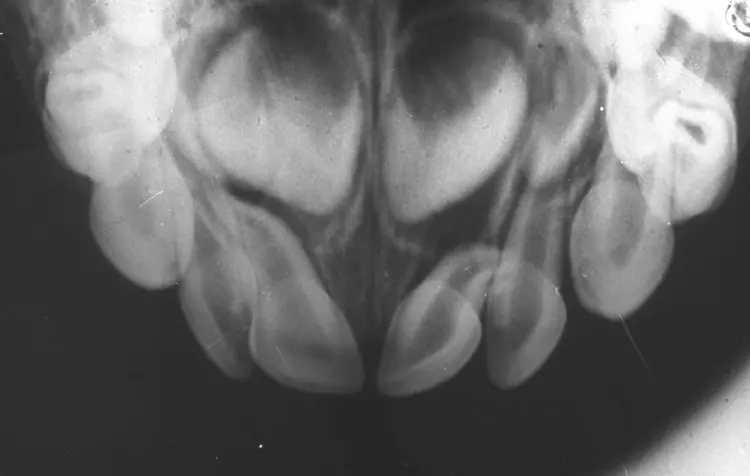

Wie bei der bleibenden Dentition stellen die Intrusionen ein besonderes Problem dar: Bei 4 bis 22% der Traumata im Milchgebiss bei sehr kleinen Kindern im Alter von 1 bis 3 Jahren [15] resultiert eine relevante Schädigung des Zahnkeimes und damit nachfolgenden Zahnes [16] wie Schmelzhypoplasien, Kronenverlagerungen, odontomähnliche Verformungen, Kronen-/Wurzelabknickung, Einstellung der Wurzelbildung, Infektion des Zahnkeimes und Schmelzschädigung sowie Durchbruchsstörungen beim bleibenden Zahn (Abb. 6a u. b).

Prinzipiell steht bei der Intrusion die abwartende Therapie mit der Möglichkeit einer spontanen Reeruption innerhalb weniger Wochen der zügigen Entfernung gegenüber, die den Druck auf den bleibenden Zahn sofort mindert, aber oft nicht ohne Narkose erfolgen kann. Randomisierte und damit hochwertige Vergleichsstudien existieren nicht und somit kann nur anhand von biologischer Plausibilität geraten werden, bei unkomplizierten Fällen primär der Reeruption eine Chance zu geben. Die Empfehlung, intrudierte Milchzähne reeruptieren zu lassen, basiert auf der bukkalen Position der Intrusion zum Zahnkeim (siehe Abb. 5).